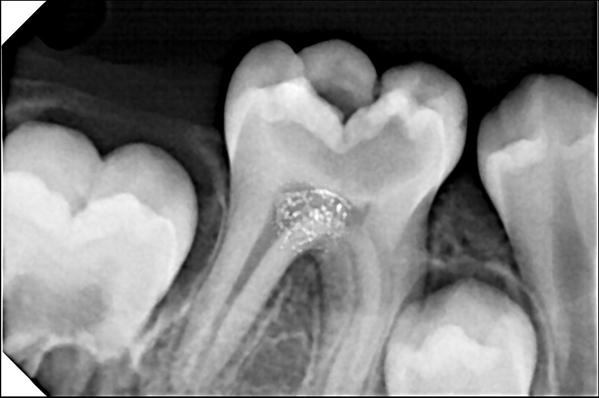

1. Consultation & X-Ray

• Dentist examines the tooth

• X-ray taken to assess roots and bone

Simple Extraction

• Tooth is visible

• Removed using forceps

Surgical Extraction

• Required for broken or impacted teeth

• May involve a small incision